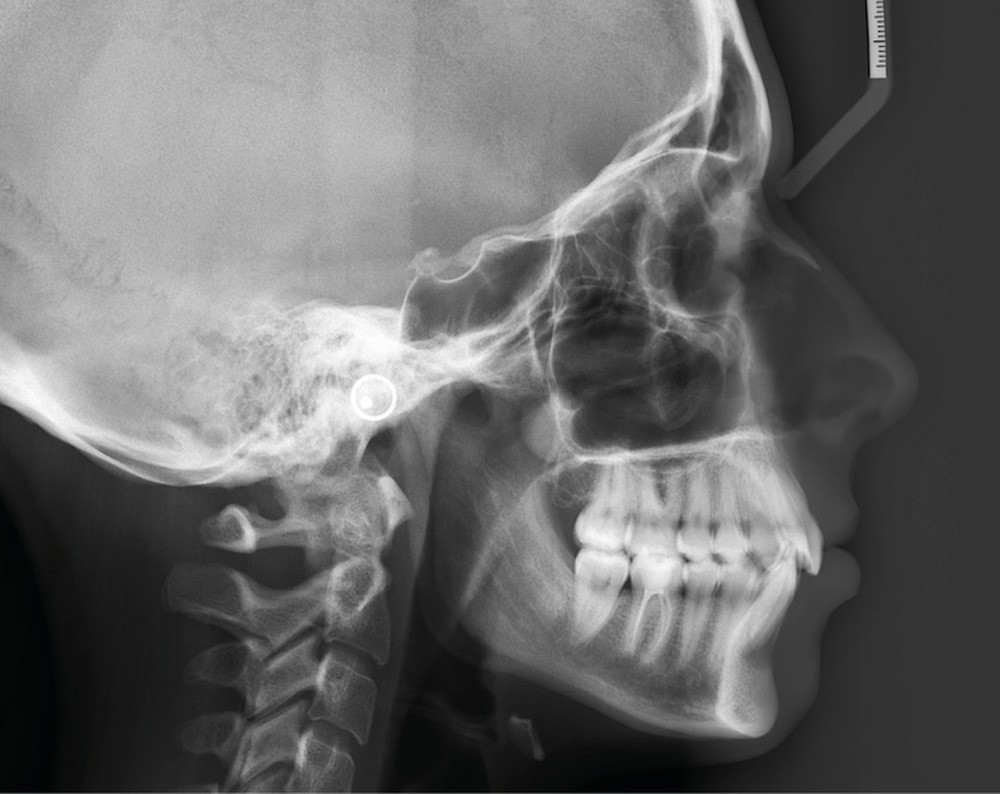

Examens complémentaires (fig. 3a,b)

À la radiographie panoramique, 31 présente une importante image apicale, confirmée par une radiographie rétroalvéolaire et également visible sur la téléradiographie de profil.

Cette dernière montre un schéma squelettique de Classe I et une typologie verticale normodivergente. Les rapports incisifs sont normaux et l’épaisseur des tissus mentonniers est insuffisante pour obtenir la fermeture buccale sans contraction. La symphyse est fine et l’incisive est centrée sur celle-ci.